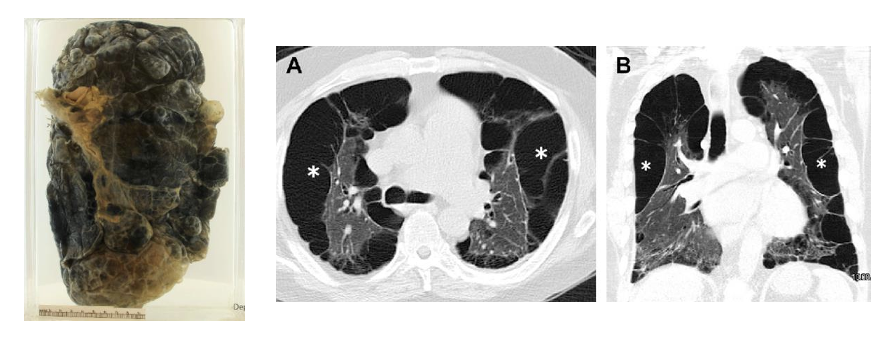

A 77-year-old heavy smoker with progressive breathlessness and weight loss presents to A&E. He has cor pulmonale and presents in respiratory failure. He dies shortly after admission. Pathology specimen of his lung and CT scan of his chest shows the following findings.

What examination finding would you have found in this patient before death?

a. Barrel chest

b. Bronchial breathing

c. Increased tactile vocal fremitus

d. Pectus excavatum

e. Stony dullness

A

Barrel chest